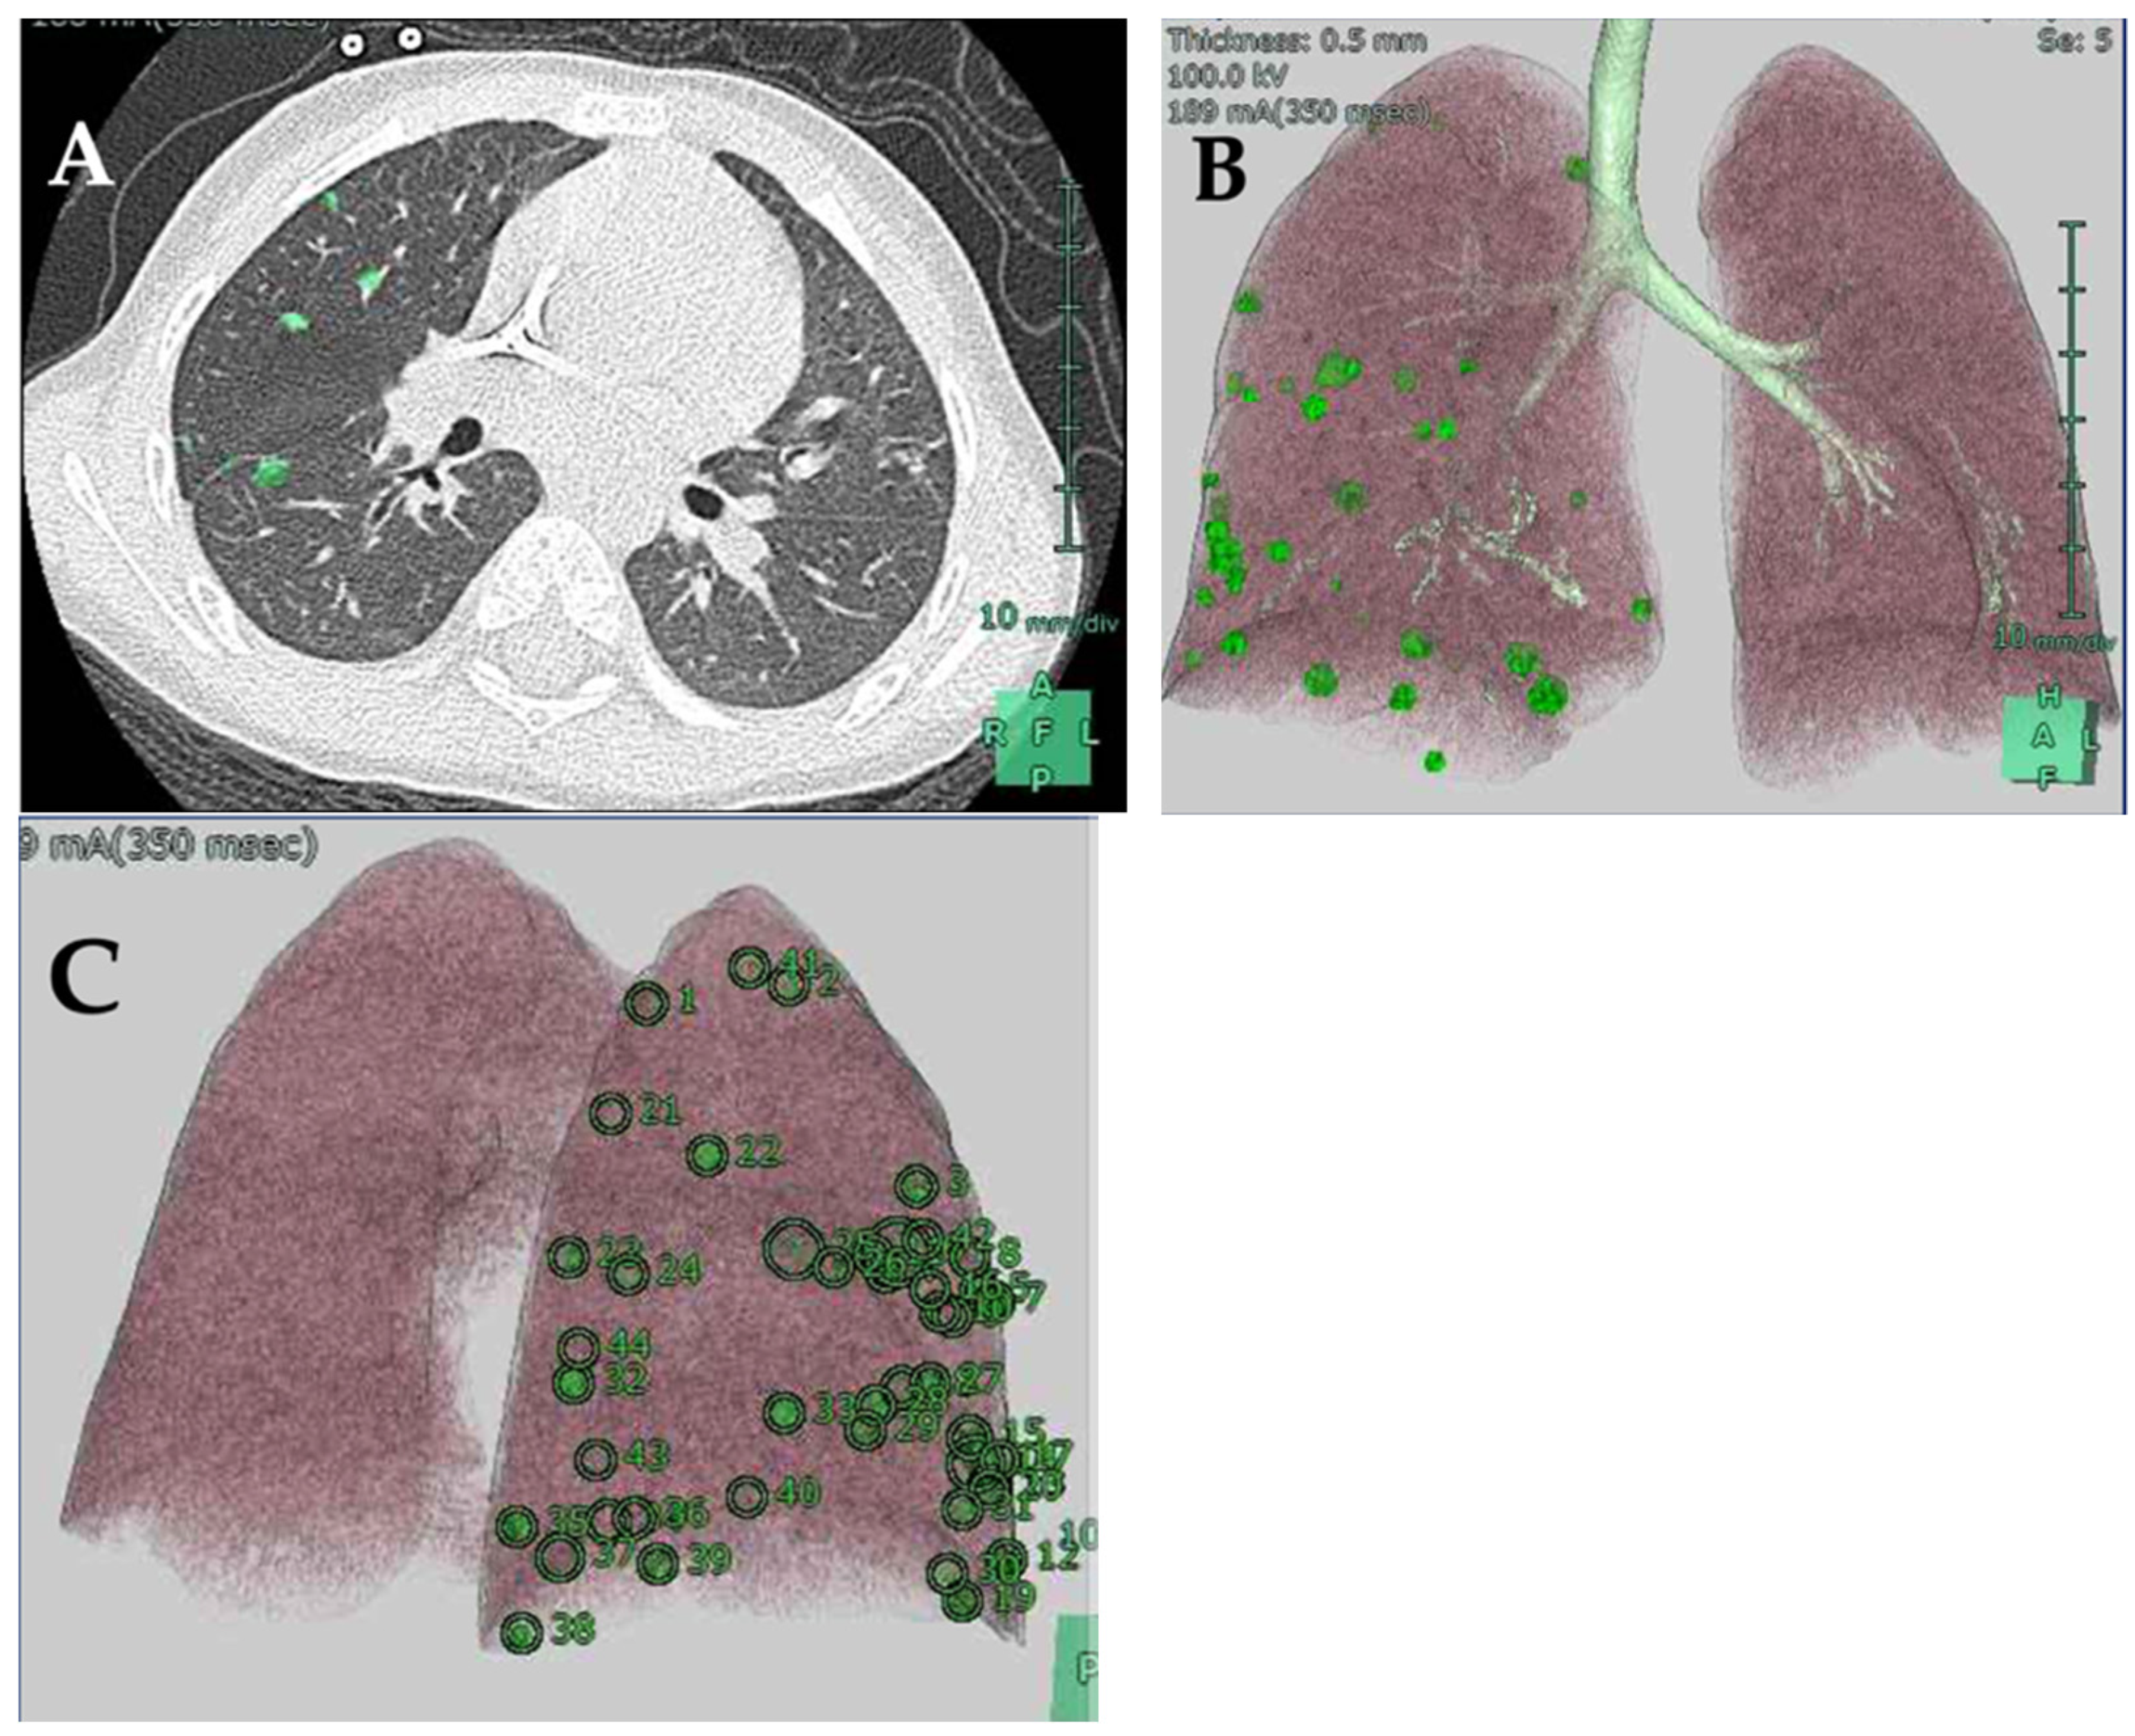

- Chu, X.P.; Chen, Z.H.; Lin, S.M.; Tang, W.F.; Zhang, J.T.; Lai, Y.M.; Fu, R.; Qiu, Z.B.; Lin, J.T.; Nie, Q.; et al. Precise resection of multiple pulmonary nodules using a three-dimensional reconstruction model: A case report. Thorac. Cancer 2021, 12, 970–973. [Google Scholar] [CrossRef]

- Wu, W.; Wu, Y.; Shen, G.; Zhang, G. Preoperative virtual simulation for synchronous multiple primary lung cancers using three-dimensional computed tomography lung reconstruction: A case report. J. Cardiothorac. Surg. 2021, 16, 10. [Google Scholar] [CrossRef]

- Akiba, T. Utility of three-dimensional computed tomography in general thoracic surgery. Gen. Thorac. Cardiovasc. Surg. 2013, 61, 676–684. [Google Scholar] [CrossRef] [PubMed]

- Akiba, T.; Morikawa, T.; Ohki, T. Thoracoscopic lung segmentectomy simulated by a tailor-made virtual lung: Computed bronchography and angiography. Thorac. Cardiovasc. Surg. 2013, 61, 151–153. [Google Scholar] [PubMed]